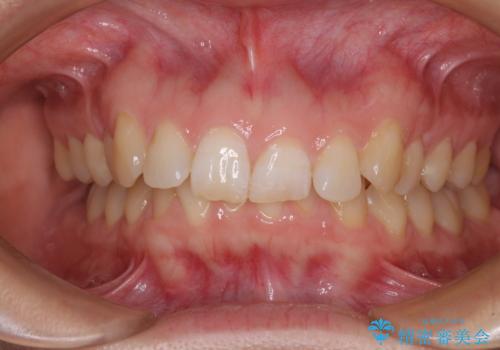

- 上顎前歯の前方に傾斜した咬み合わせを気にして来院された患者様です。

奥歯の咬み合わせを見ると、上顎が下顎に対して相対的に前方にありました。

深い咬み合わせを改善するためには、上顎臼歯を後方に移動させつつ、下顎の小臼歯を直立させる必要があります。